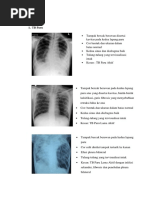

TB PARU KIRI AKTIF (K4)

25

Gambaran : Bercak kesuraman mengawan, diffuse, di lapangan atas Paru: Apeks

atau lobus Superior kiri (Dapat di satu paru atau duplek.)

Patologi : Pembentukan infiltrat oleh Mycobacterium Tuberkulosa.

TB PARU DUPLEKS AKTIF